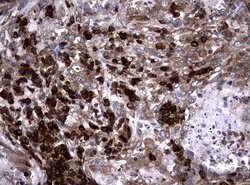

NME1 Mouse anti-Canine, Human, Rat, Clone: UMAB94, liquid, UltraMAB™

NME1 was identified because of its reduced mRNA transcript levels in highly metastatic cells. Nucleoside diphosphate kinase (NDK) exists as a hexamer composed of ′A′ (encoded by this gene) and ′B′ (encoded by NME2) isoforms. Mutations in the gene have been identified in aggressive neuroblastomas. Two transcript variants encoding different isoforms have been found for this gene. Co-transcription of this gene and the neighboring downstream gene (NME2) generates naturally-occurring transcripts (NME1-NME2), which encodes a fusion protein comprised of sequence sharing identity with each individual gene product.Specifications

| Immunocytochemistry, Immunofluorescence, Immunohistochemistry (Paraffin) | |